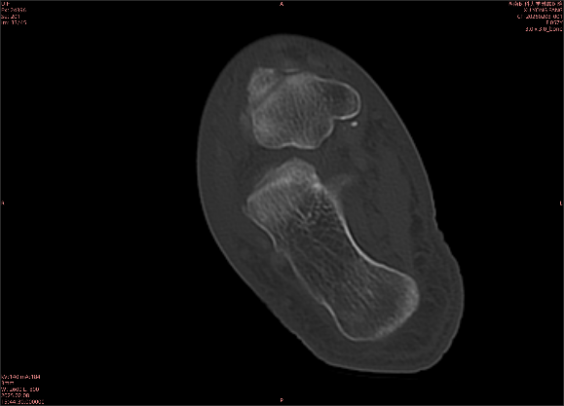

為什么DR和CT基本無法診斷?(專業(yè)科普)

由于無骨皮質(zhì)中斷,尚不足以引起X線衰減系數(shù)的明顯改變,X線平片無異常征象;CT在顯示骨皮質(zhì)及軟組織異常方面明顯優(yōu)于傳統(tǒng)X線,特別是三維重建能夠有效的評(píng)價(jià)復(fù)雜骨折,骨外傷CT檢查應(yīng)用廣泛,但CT對(duì)隱性骨折的顯示亦極為有限。

舉例圖像

圖2

專業(yè)解釋看不懂沒關(guān)系,大家看圖1和圖2就可以了,這是同一個(gè)患者跟骨的磁共振和CT圖像,圖1的紅色箭頭指示的黑線就是磁共振圖像顯示的骨折線,一目了然。而對(duì)比圖2的CT圖像上并未顯示異常。